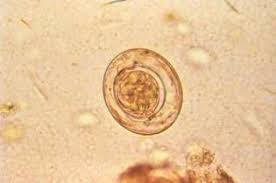

Pin On Hymenolepis Nana Dwarf Tapeworm